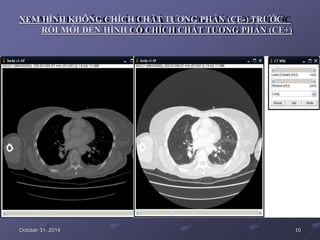

XEM HÌNH KHÔNG CHÍCH CHẤT TƯƠNG PHẢN (CE-) TRƯỚC

RỒI MỚI ĐẾN HÌNH CÓ CHÍCH CHẤT TƯƠNG PHẢN (CE+)

October 31, 2014 10

XEM HÌNH KHÔNGCHÍCH CHẤT TƯƠNG PHẢN (CE-) TRƯỚC RỒI MỚI ĐẾN HÌNH CÓ CHÍCH CHẤT TƯƠNG PHẢN (CE+) October 31, 2014 10